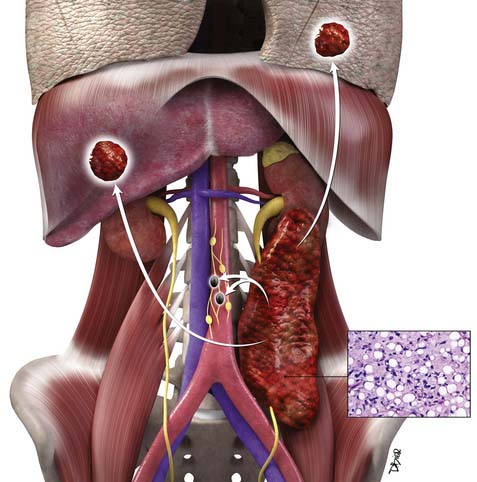

Primary Retroperitoneal Tumors | Radiology Key

radiologykey.com

radiologykey.com

retroperitoneal tumor tumors staging